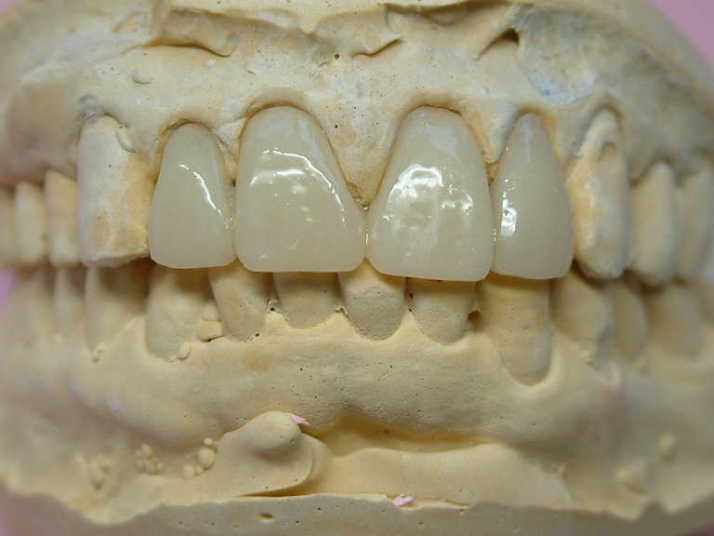

補綴物物 完成

患者さんから「出っ歯にならないよに!」

と再度念を押されたので

出来る限り内側に入れて製作しました。

模型上では、1.1下部孤形空隙が広いように

見えますが、歯肉模型にて調整して

歯肉を圧迫せず、息が漏れることが無いように

調整しました |